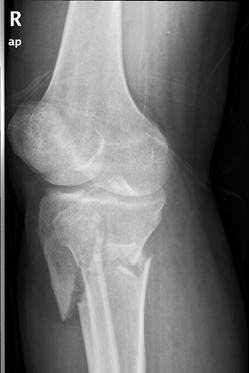

骨折是我们在日常生活中常见的一种疾病,通过手术治疗往往可以达到稳定的固定作用。手术固然重要,但术后功能康复亦不能忽视。小编最近就遇到一位胫骨平台骨折患者,该患者在4个月前发生了车祸导致胫骨平台骨折,并进行切开复位内固定手术治疗。但由于在术后一直畏痛少动,未进行积极地康复治疗,致使患侧膝关节难以像健侧一样伸直,下肢功能急剧下降。为了避免出现以上情况,今天小编就与您分享,胫骨平台骨折术后该如何正确康复。

胫骨平台是膝关节重要的负荷组成部分,也是膝关节创伤中最常见的骨折之一,多发生于强烈的外翻和内翻应力合并轴向载荷时,同时股骨髁对其下胫骨平台有压力和剪切力,可造成劈裂骨折、塌陷骨折或两者兼有。当发生胫骨平台骨折后,需要通过手术切开复位固定,术后要及时进行康复训练,以加快骨折愈合,促进患肢功能恢复。

1. 拍摄膝关节X光片复查,并根据骨折线愈合情况及专业医生建议决定是否开始进行患肢负重练习。